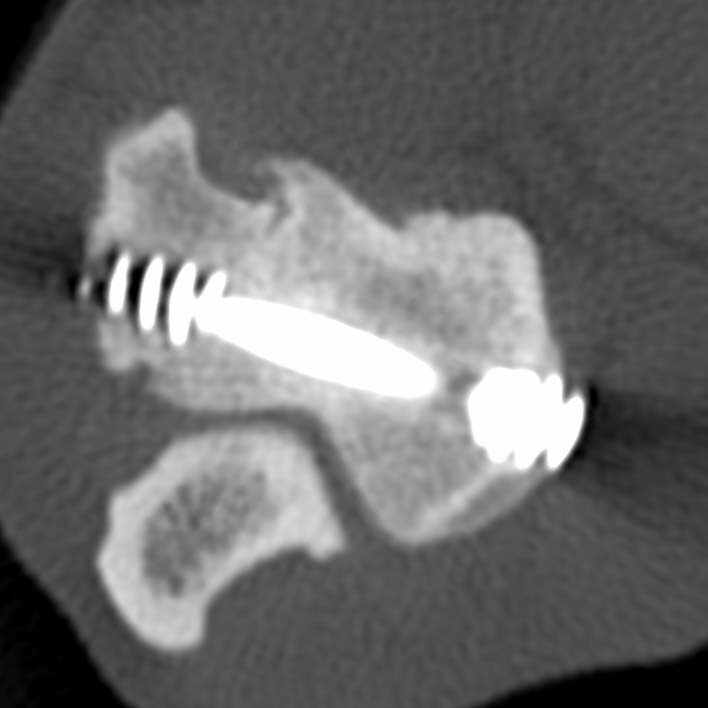

CT is the most common means of diagnosing HIF. Radiography (X-rays) will miss some of them, but if you can see one on a radiograph then further tests might not be required. Other possible causes of lameness, eg elbow dysplasia, might also need to be considered.

Most Specialists are likely to advise placing a screw across the humeral condyle, especially if your dog is limping and/ or there is elbow pain. The purposes of the screw are to prevent movement and instability and therefore improve the lameness, and to reduce the risk of the bone breaking completely.

Two of Movement’s Specialists, Ben Walton and John Innes, designed and clinically tested the humeral intracondylar repair system (HIRS) for the treatment of HIF in Spaniels and, the clinical results were published in 2020.

Placing the screw accurately is very important to avoid damaging the joint. We will often use custom, patient-specific, 3D-printed surgical guides like THESE, or a careful planning method like THIS.